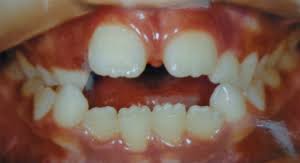

Ele é usado em casos que o osso maxilar é muito estreito.